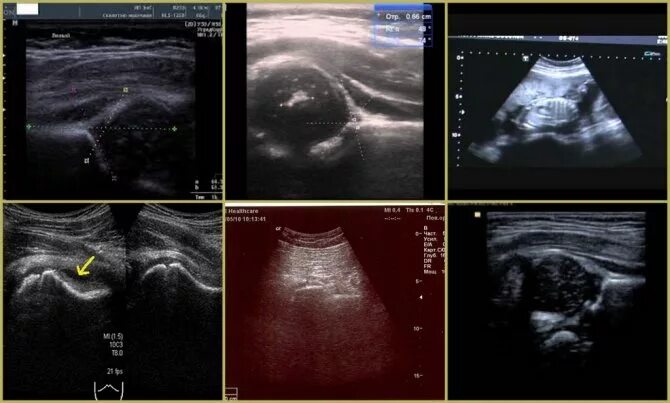

Узи тазобедренного сустава у взрослых что показывает